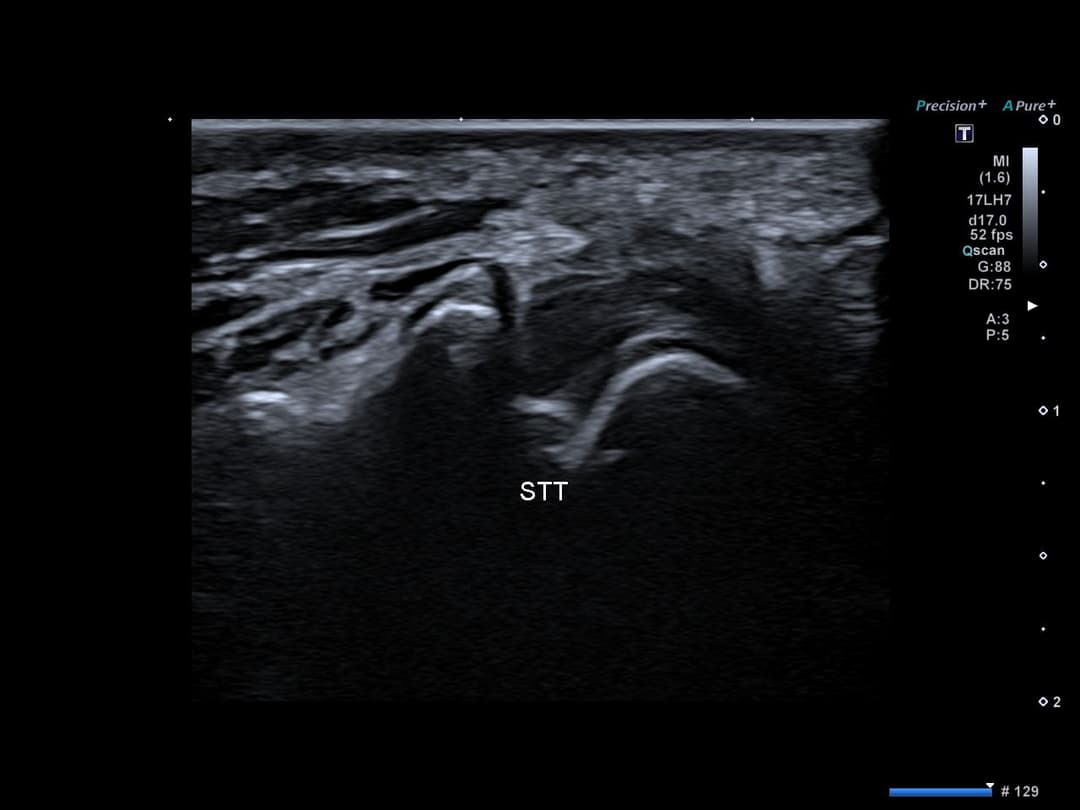

Intégrité des tendons de la première loge tendineuse et de leur rétinaculum sans signe de De Quervain

Intégrité de l'articulation scapho-trapézienne